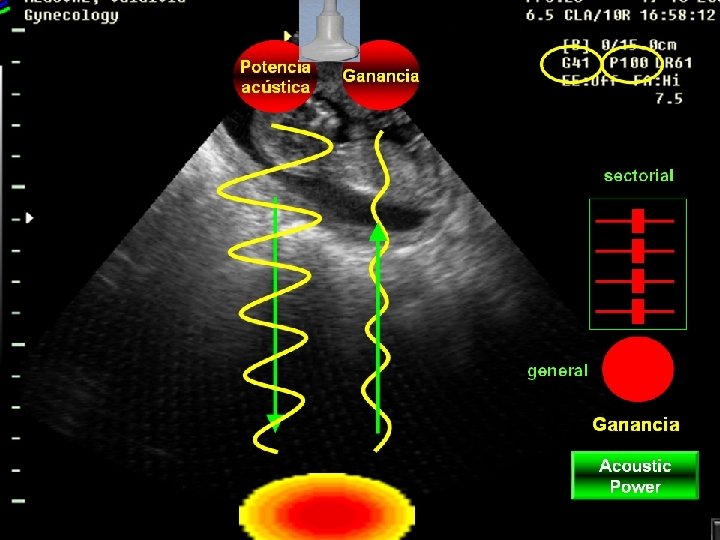

Efectos Biológicos • • La seguridad del ultrasonido ha sido un tema de debate permanente. Las implicancias en el caso del ultrasonido obstétrico son muy diferentes de aquellas en el caso del ultrasonido terapéutico o quirúrgico. Ultrasonido Terapéutico Diagnóstico 2 D Energía 0. 5 – 3. 0 W/cm 2 0. 001 – 0. 1 W/cm 2 Doppler Color 1000 W/cm 2